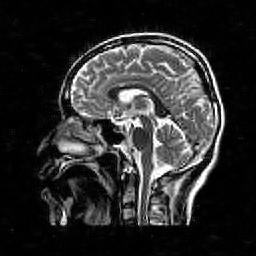

Hence both and should recover equally well. In the top row of Figure 1 we present the result of the flip test for a Gaussian random matrix. As is evident, the reconstructions and are comparable, thus indicating the RIP.

Having considered type II problems, let us now examine the flip test for a type I problem. As discussed, in applications such as MRI, X-ray CT, radio interferometry, etc, the matrix is imposed by the physical sensing device and arises from subsampling the rows of the DFT matrix .111In actual fact, the sensing device takes measurements of the continuous Fourier transform of a function . As discussed in BAACHGSCS ; BAGSAIEP , modelling continuous Fourier measurements as discrete Fourier measurements can lead to inferior reconstructions, and worse, inverse crimes. To avoid this, one must consider an infinite-dimensional compressed sensing approach, as in (2). See AHPRBreaking ; BAGSAIEP for details, as well as PruessmannUnserMRIFast for implementation in MRI. However, for simplicity, we shall continue to work with the finite-dimensional model in the remainder of this paper. Whilst one often has some freedom to choose which rows to sample (corresponding to selecting particular frequencies at which to take measurements), one cannot change the matrix .

It is well known that in order to ensure a good reconstruction, one cannot subsample the DFT uniformly at random (recall that the sparsifying transform is a wavelet basis), but rather one must sample randomly according to an appropriate nonuniform density AHPRBreaking ; Candes_Romberg ; Lustig ; WangAcre . See the bottom left panel of Figure 1 for an example of a typical density. As can be seen in the next panel, by doing so one achieves a great recovery. However, the result of the flip test in the bottom right panel clearly demonstrates that the matrix does not satisfy an RIP. In particular, the ordering of the wavelet coefficients plays a crucial role in the reconstruction quality. To explain this, and in particular, the high-quality reconstruction seen in the unflipped case, one evidently requires a new analytical framework.

Note that the flip test in Figure 1 also highlights another important phenomenon: namely, the effectiveness of the subsampling strategy depends on the sparsity structure of the image. In particular, two images with the same total sparsity (the original and the flipped ) result in wildly different errors when the same sampling pattern is used. Thus we conclude that there is no one optimal sampling strategy for all sparse vectors of wavelet coefficients.